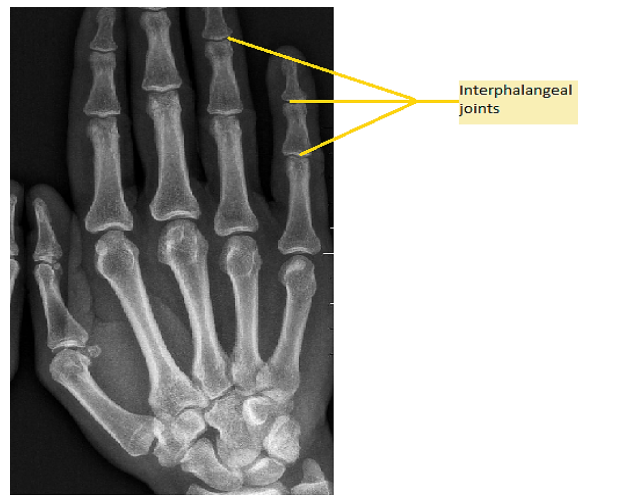

A joint in a human body is the connection between two bones. It is of three main types (immovable, slightly movable, and freely movable) based on whether it allows movement or not. Interphalangeal joints are present between the phalanges (bones in the thumb and fingers).

Option (B) is correct. Hinge joints function much like the hinge of the door thereby allowing movement of the bones only in one direction back and forth further restricting the movement in other planes. These joints are present in fingers, toes, elbows, knees, and ankles. Since interphalangeal joints are known to be present in fingers and toes (made of phalanges) that provide movement of the bones towards the palm and foot therefore these interphalangeal joints are also called hinge joints.

Note: The hinge joint is that joint in which the two bones are connected by these joints that allow movement only in one direction. The interphalangeal joints are called hinge joints because these allow movement of the phalanges only in one direction.